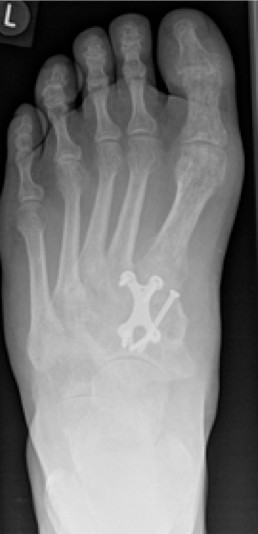

1.-Prä operatives MRT des linken Fußes vom Oktober 2016